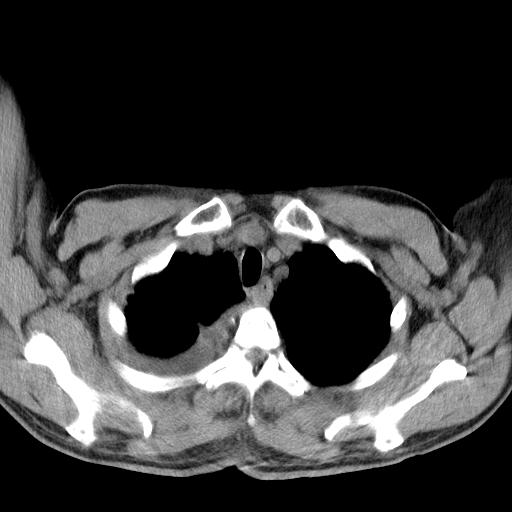

以下是引用zjzjr在2010-3-21 17:39:00的发言:[br]右下中心型肺癌并阻塞性肺炎/不张,纵膈淋巴结肿大,右侧大量胸腔积液,左侧少量胸腔积液

以下是引用zxl51642在2010-3-21 17:06:00的发言:[br]右下中心型肺癌并阻塞性肺炎/不张,纵膈淋巴结肿大,右侧大量胸腔积液,左侧少量胸腔积液,少量腹水。建议纤维支气管镜进一步检查。